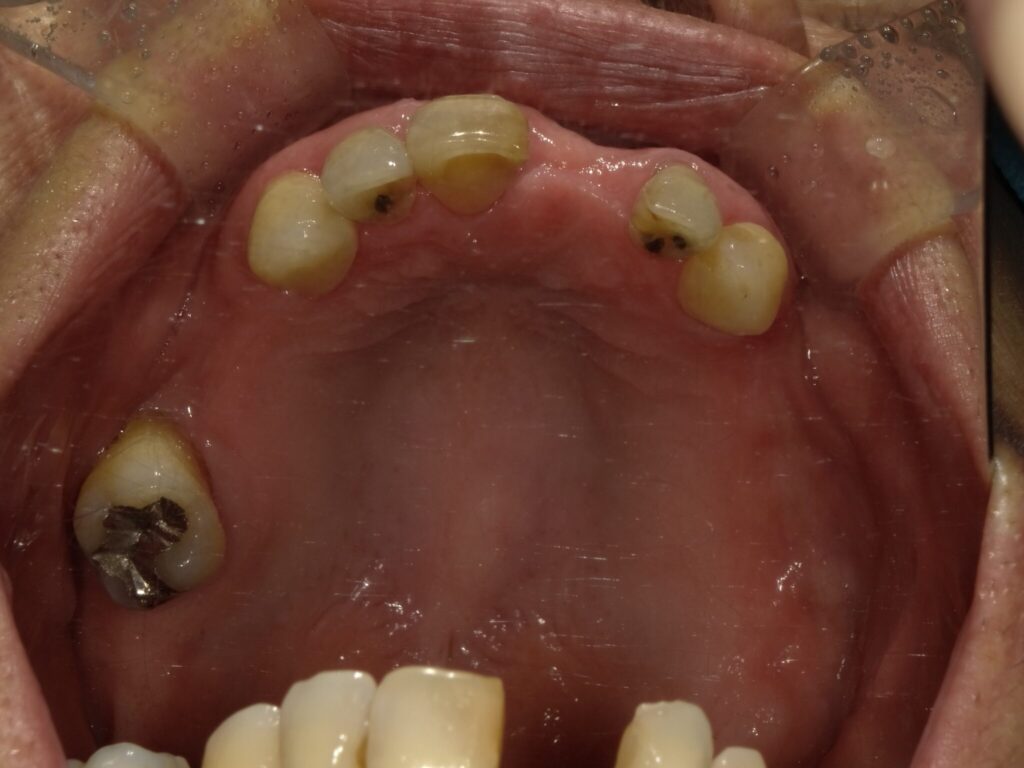

全顎治療症例

| 主訴 | 全体的に見た目を綺麗にしたい。奥歯でしっかり噛みたい。 |

| 診断名・ 主な症状 |

臼歯部欠損 |

| 治療内容 | インプラント埋入(左下5・6,右下5・6,左上4・6) サイナスリフト(左上4・6) ジルコニアBr(右上6−左上3) E –MAX CAD(右下4) セラミックインレー(左下4) |